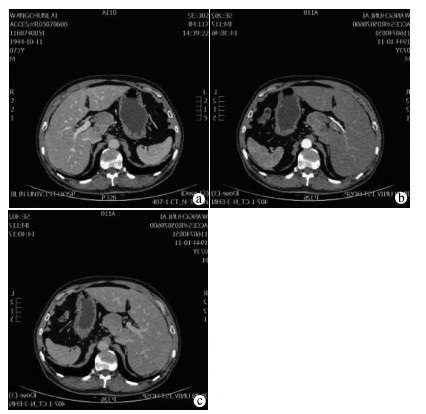

Long-term survival of malignant melanoma with porta hepatis metastasis: A case report

Shuxuan LI, Kai KOU, Guoyue LYU

2021, 37(1): 160-162. DOI: 10.3969/j.issn.1001-5256.2021.01.033

Abstract(1388) HTML (946) PDF (2605KB)(68)

Abstract: